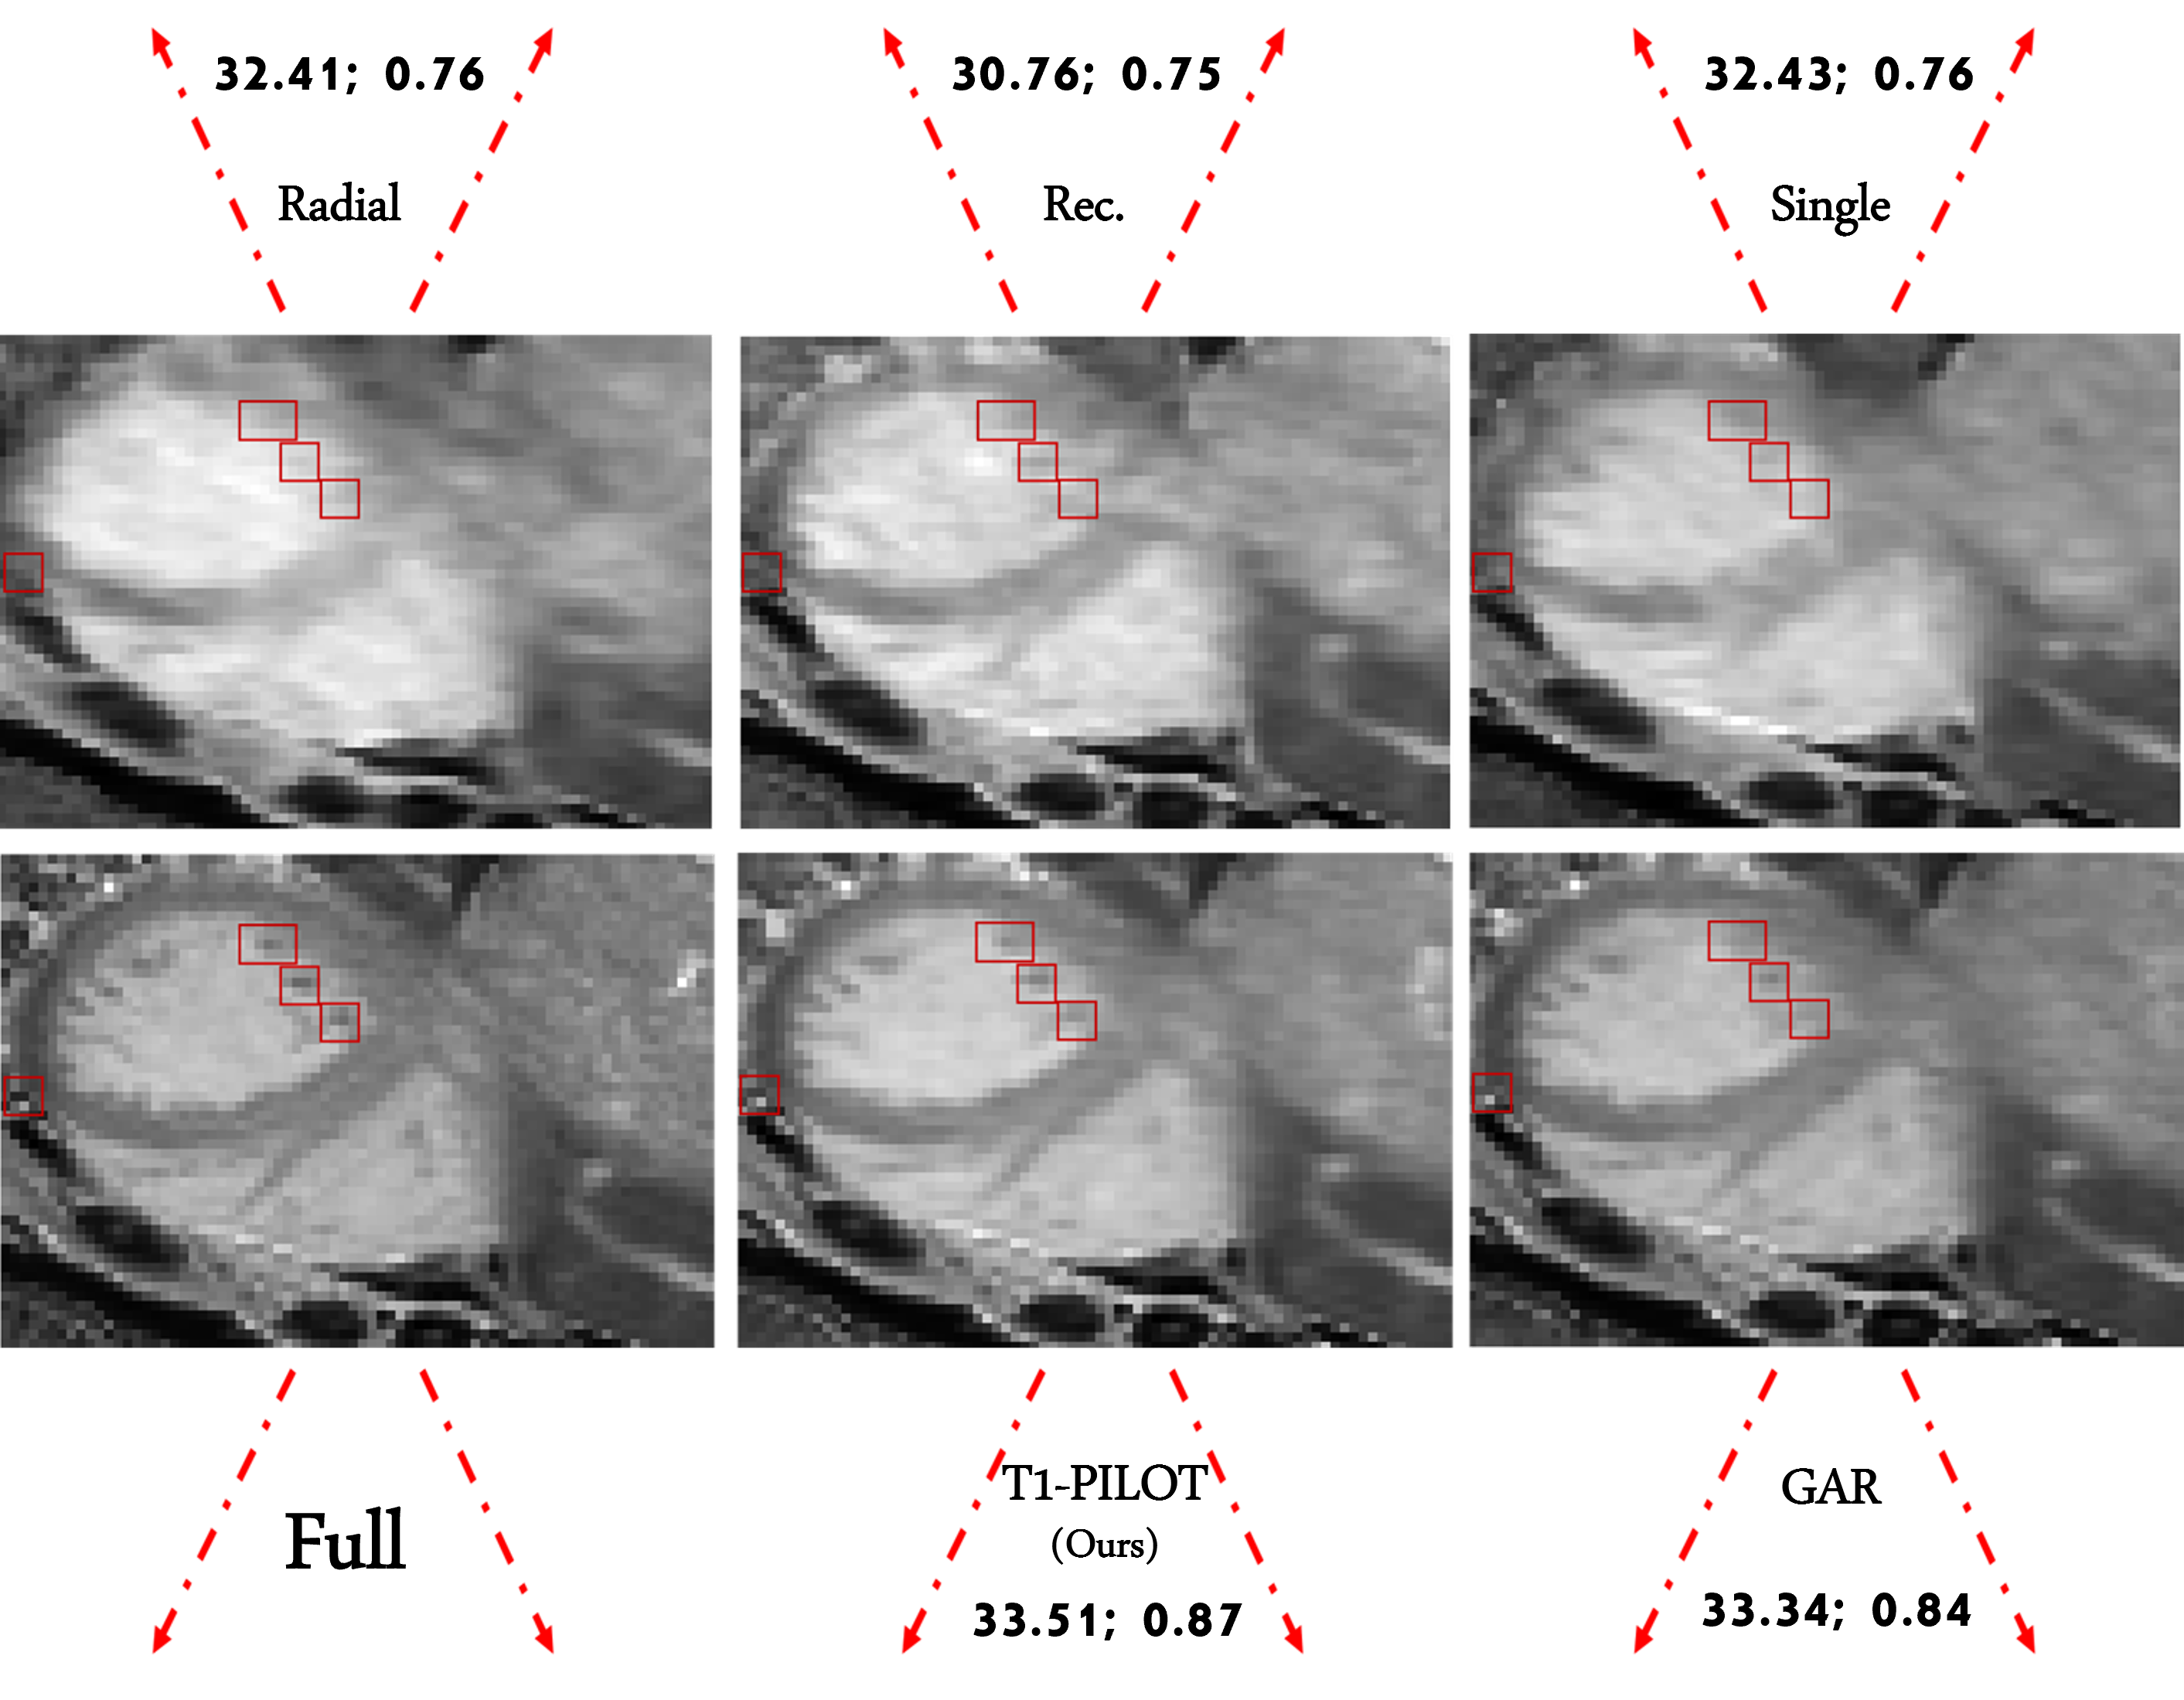

Figure 2: Map Estimations across methods - Full indicates map estimation without undersampling. For each baseline, we specify ROI PSNR (left) and VIF (right) compared to the fully-sampled map estimation. Our method’s relative advantage over baselines is highlighted in red squares.

Figure 2 illustrates T1 maps estimated by our method and by each of the four baselines trained for acceleration factors of 6464 shots per-frame, compared to the map derived from fully-sampled data (upper-left). Maps are shown both in their entirety and with focus on the myocardium. Our method yields sharper and more accurate estimations, surpassing baselines in capturing fine details and subtle variations, particularly in smaller regions of the map (framed in red). We attribute this improvement to the effectiveness of learned, multi-frame non-Cartesian undersampling, which prioritizes high-frequency components essential for preserving such subtle features. As evident from the figure, baseline sampling patterns with non-learned (GAR, Radial) or single-frame (denoted Single, bottom-right) acquisition patterns struggle in identifying such patterns.